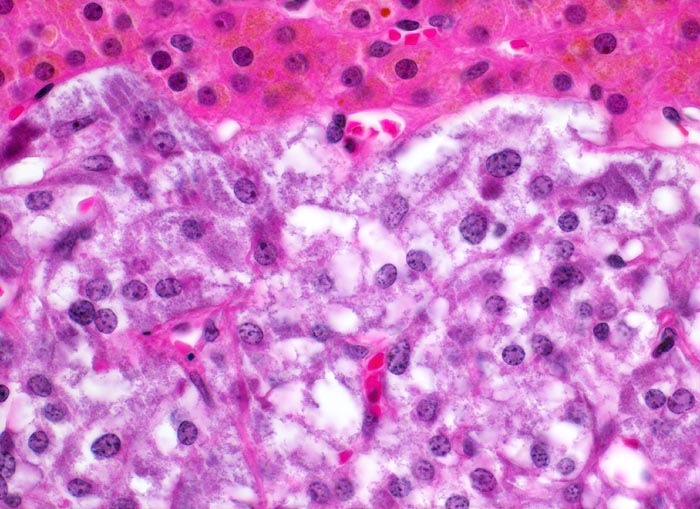

• „Zellballen“ umgeben von schmalen Bindegewebssepten mit kapillären Gefässen.

• Polygonale Tumorzellen mit reichlich granuliertem basophilem Zytoplasma und rundovalen Kernen mit uniform feinkörnigem Pfeffer und Salz Chromatin sowie prominentem Nukleolus.

• Herdförmig Tumorzellen mit sehr grossen polymorphen Zellkernen (links oben).